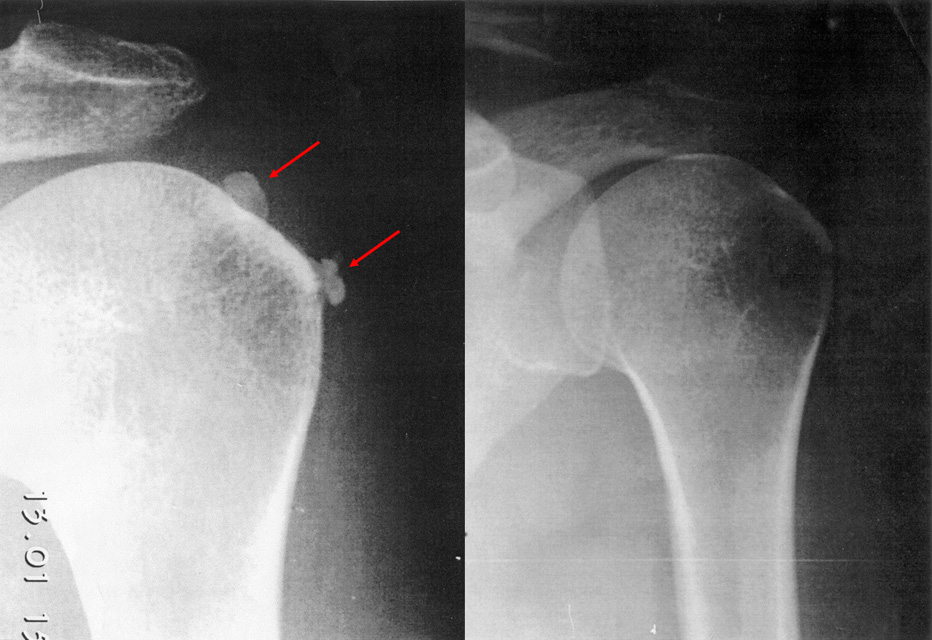

- Ασβέστωση